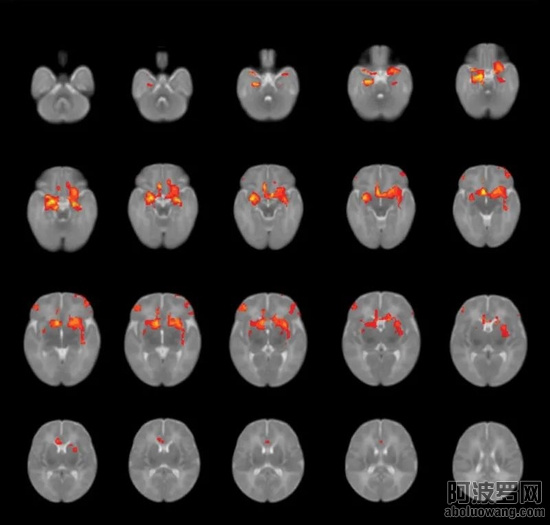

他们在对出生后3个月的婴儿大脑进行磁共振成像扫描后发现,孕期焦虑或抑郁较严重的妈妈似乎会影响胎儿大脑的神经连接。

3.jpg

布朗大学的儿科副教授Sean Deoni博士和同事们开发和应用磁共振成像(MRI)等技术研究婴儿的认知发育,追踪运动、视觉、语言技能的发展。然而这两年他们逐渐注意到,来研究所测试发育的孩子要比过去花更长的时间才能通过评估。